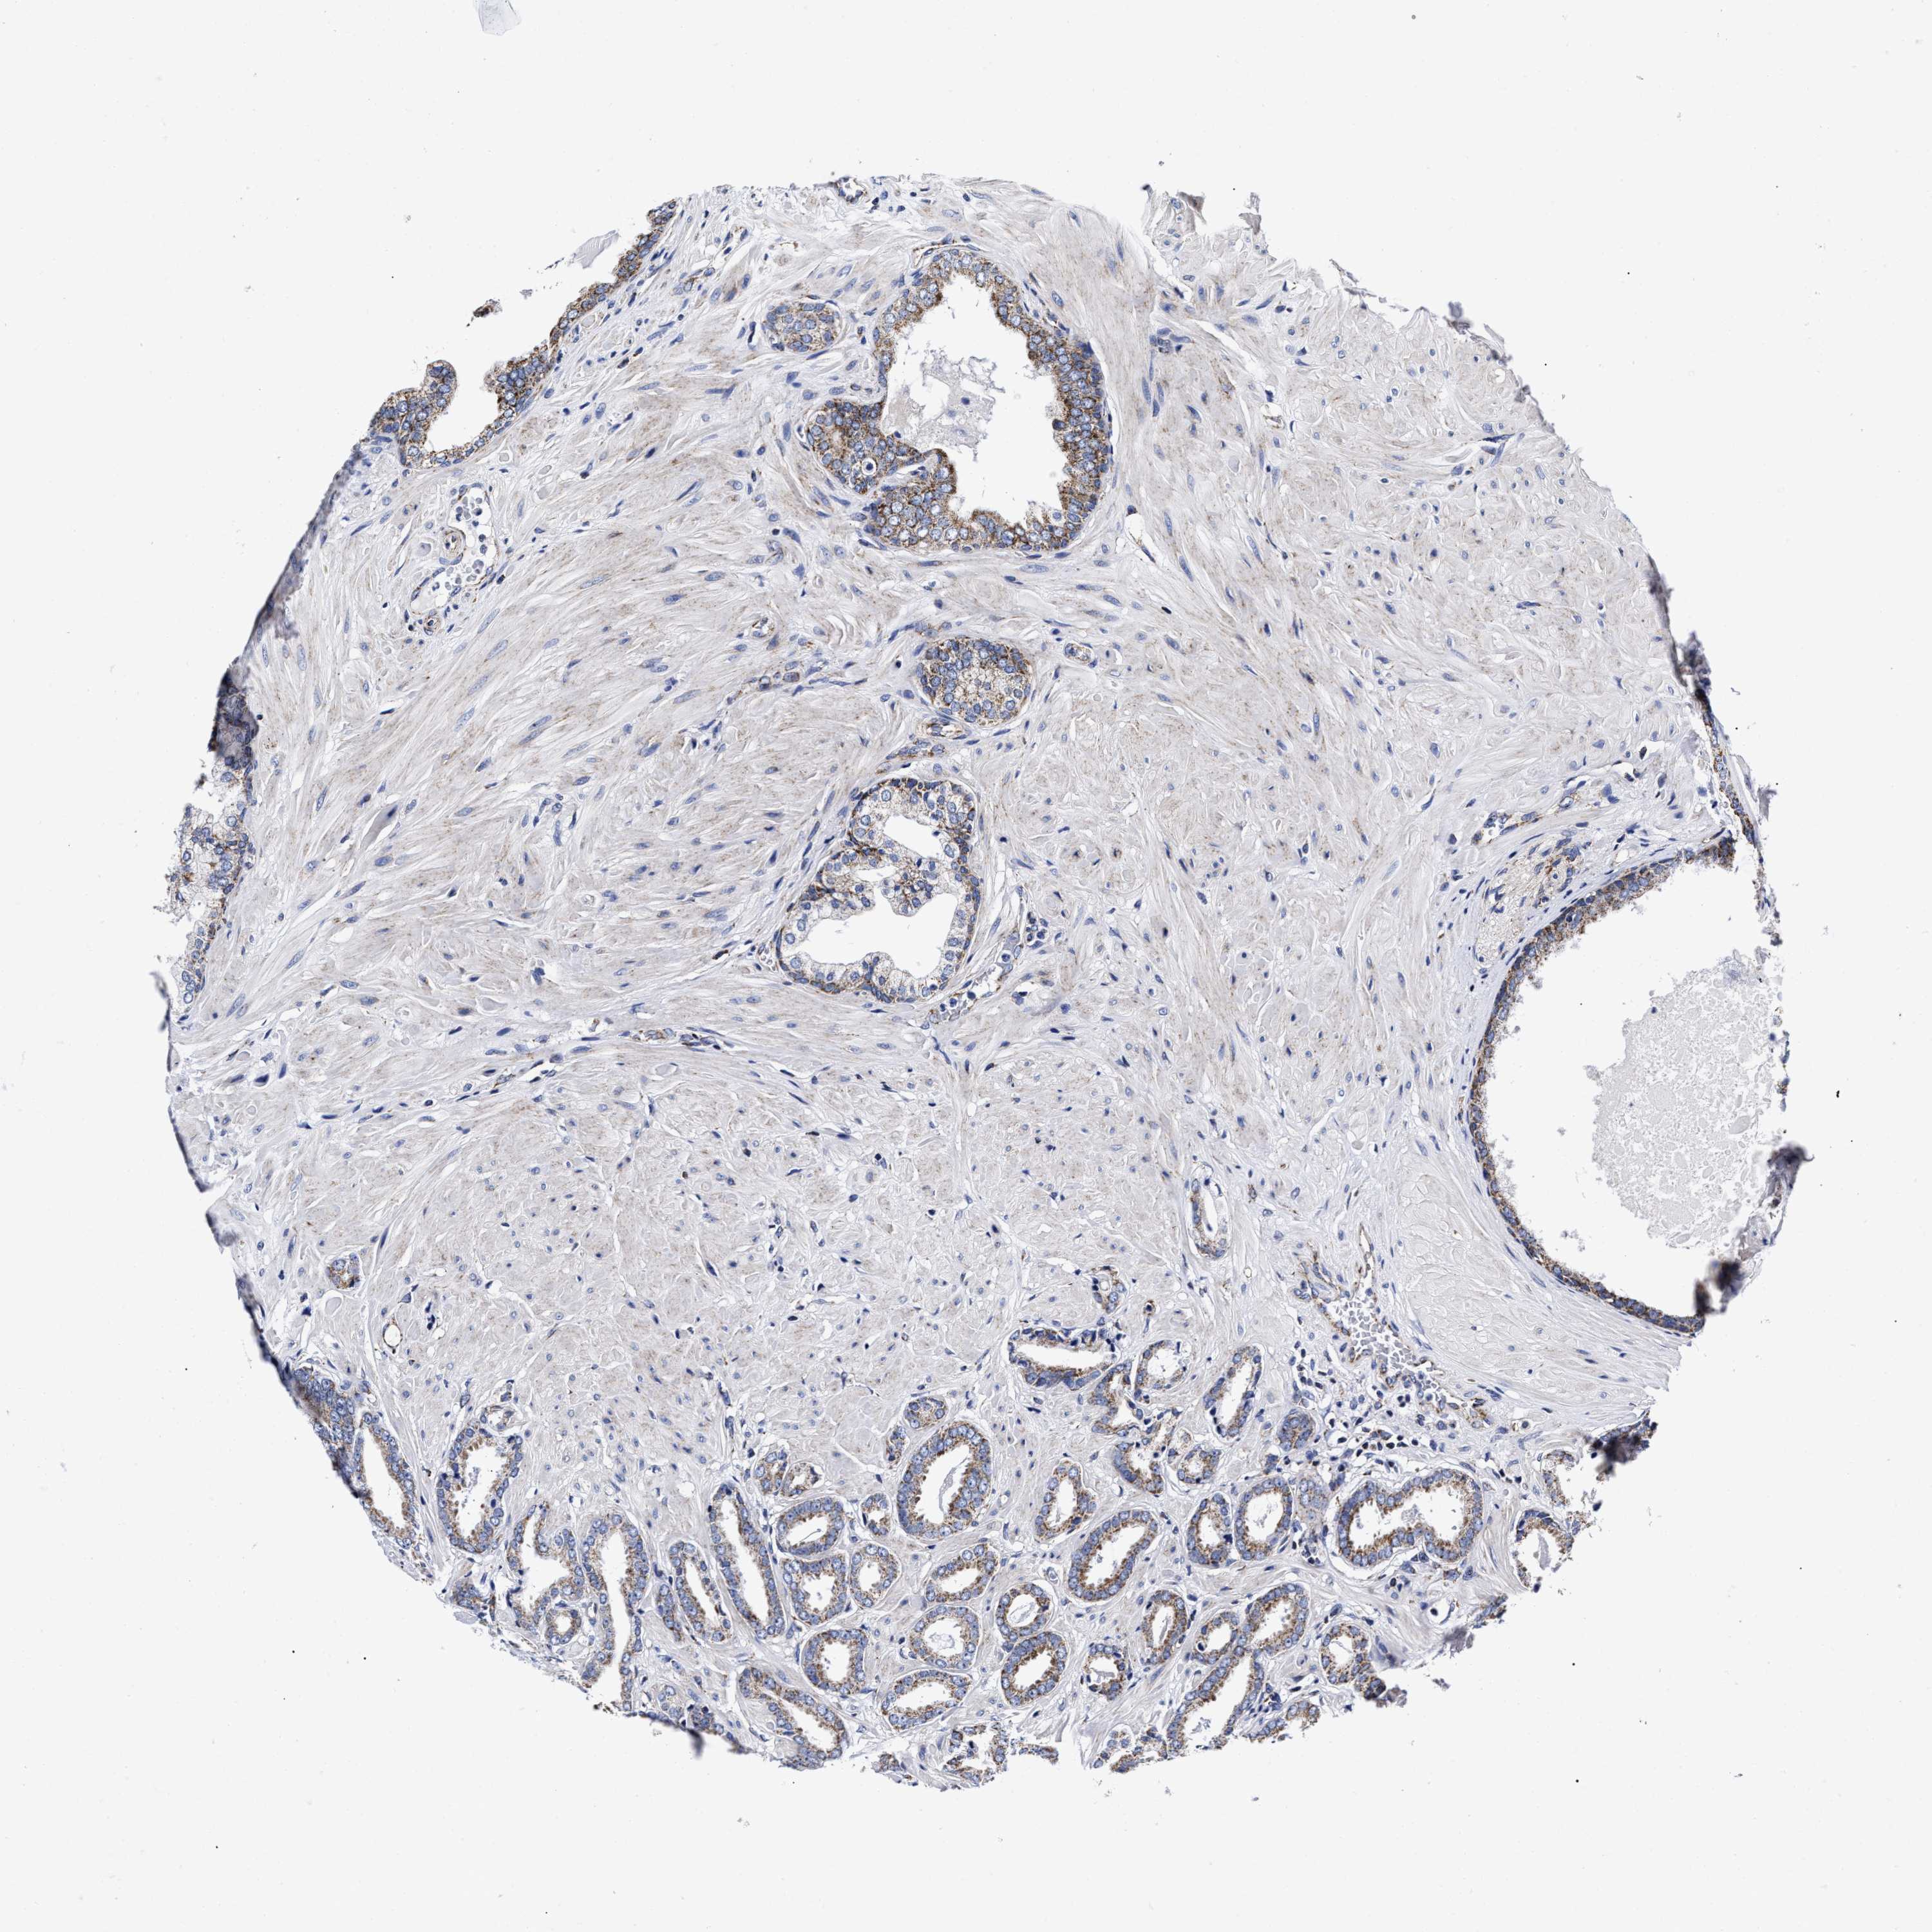

PROSTATE CANCER - Protein expressioni

A mouse-over function shows sample information and annotation data. Click on an image to view it in a full screen mode. Samples can be filtered based on level of antibody staining by selecting one or several of the following categories: high, medium, low and not detected. The assay and annotation is described here.

Note that samples used for immunohistochemistry by the Human Protein Atlas do not correspond to samples in the TCGA dataset.

Antibody stainingi

Antibody staining in the annotated cell types in the current human tissue is reported as not detected, low, medium, or high, based on conventional immunohistochemistry profiling in selected tissues. This score is based on the combination of the staining intensity and fraction of stained cells.

Each image is clickable and will lead to virtual microscopy that enables deeper exploration of all samples and also displays staining intensity scores, fraction scores and subcellular localization as well as patient and tissue information for each sample.

Antibody HPA020961

Antibody HPA059109

Staining

High

Medium

Low

Not detected

Intensity

Strong

Moderate

Weak

Negative

Quantity

>75%

75%-25%

<25%

None

Location

Nuclear

Cytoplasmic/membranous

Cytoplasmic/membranous,nuclear

Adenocarcinoma, High grade

Adenocarcinoma, Low grade